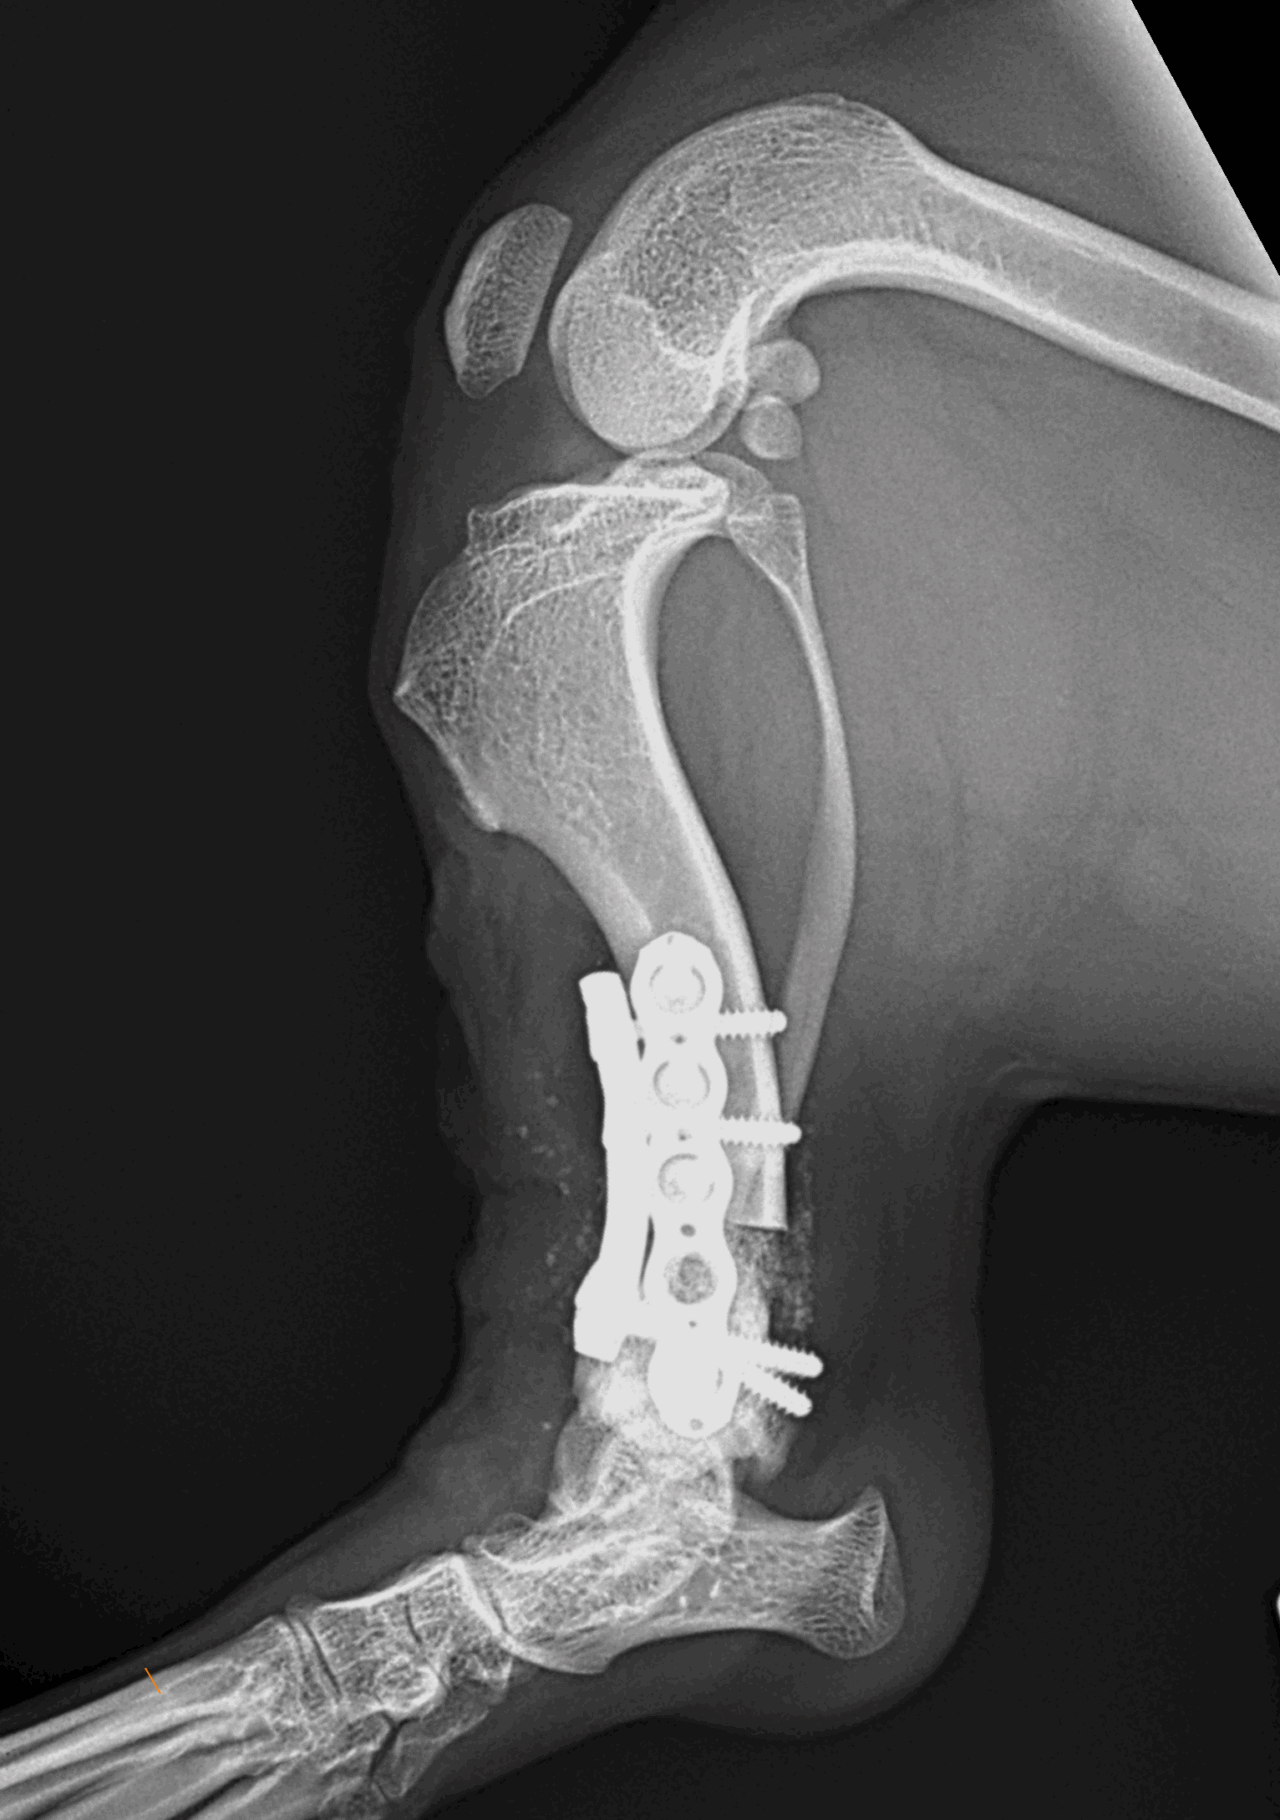

膝蓋骨外方脱臼に対し、整復しても再発を繰り返す場合、その背景に「骨の形そのものの異常」が潜んでいることがあります。今回のミニチュアダックスさんは、脛骨遠位の内反変形(Pes Varus)を基盤とした外方脱臼であり、オープンウェッジ骨切り術+オーソゴナルプレート固定による矯正手術を実施しました。

・脛骨遠位オープンウェッジ骨切り

・ロッキングプレートによる固定

・骨切り部へのβ-TCP充填

・膝蓋骨の大腿骨滑車内への整復を確認、アライメント手術